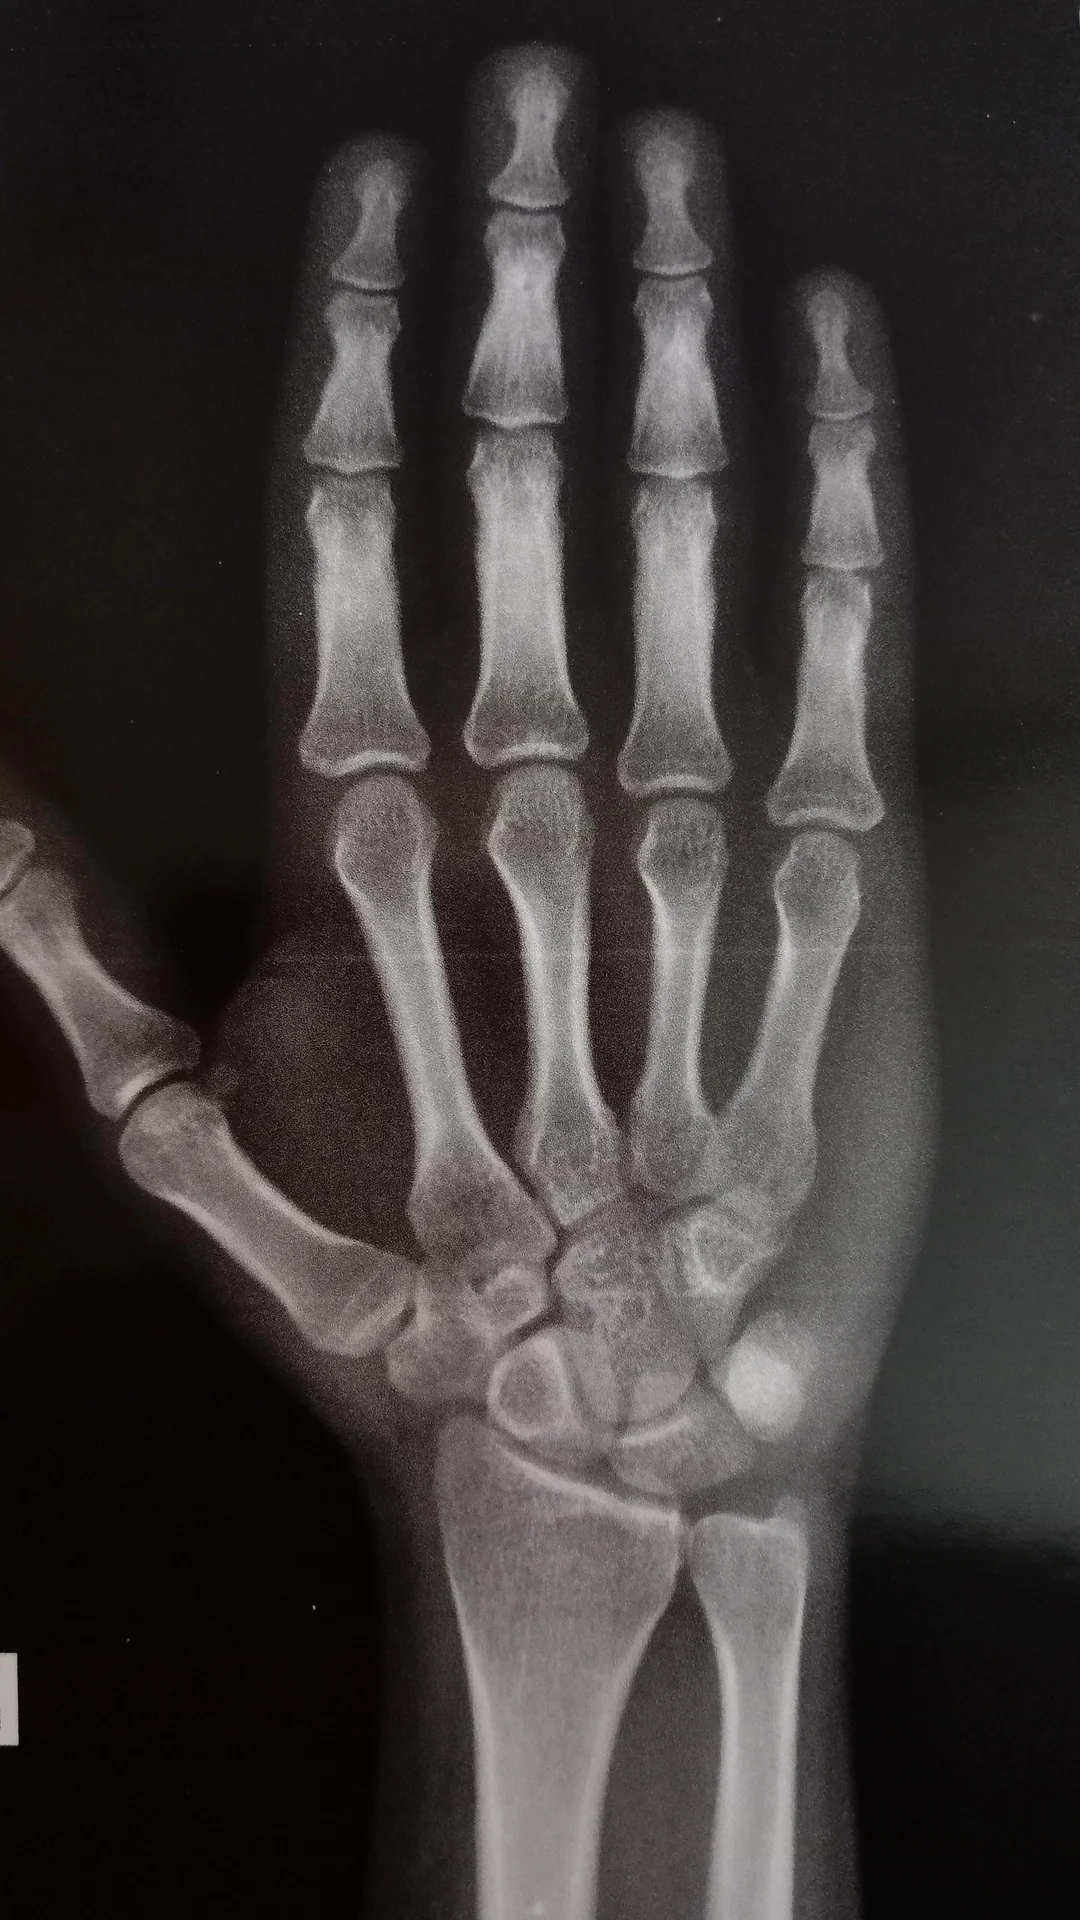

this is what he sent me just now from his doctors visit the other day (they were in disbelief and he was very satisifed), but I know his growth plates looked a bit less closed than this last year but he's 19 now so its to be expected it closes more

Are my growth plates closed im 20m v0 r38snq0pjkhc1